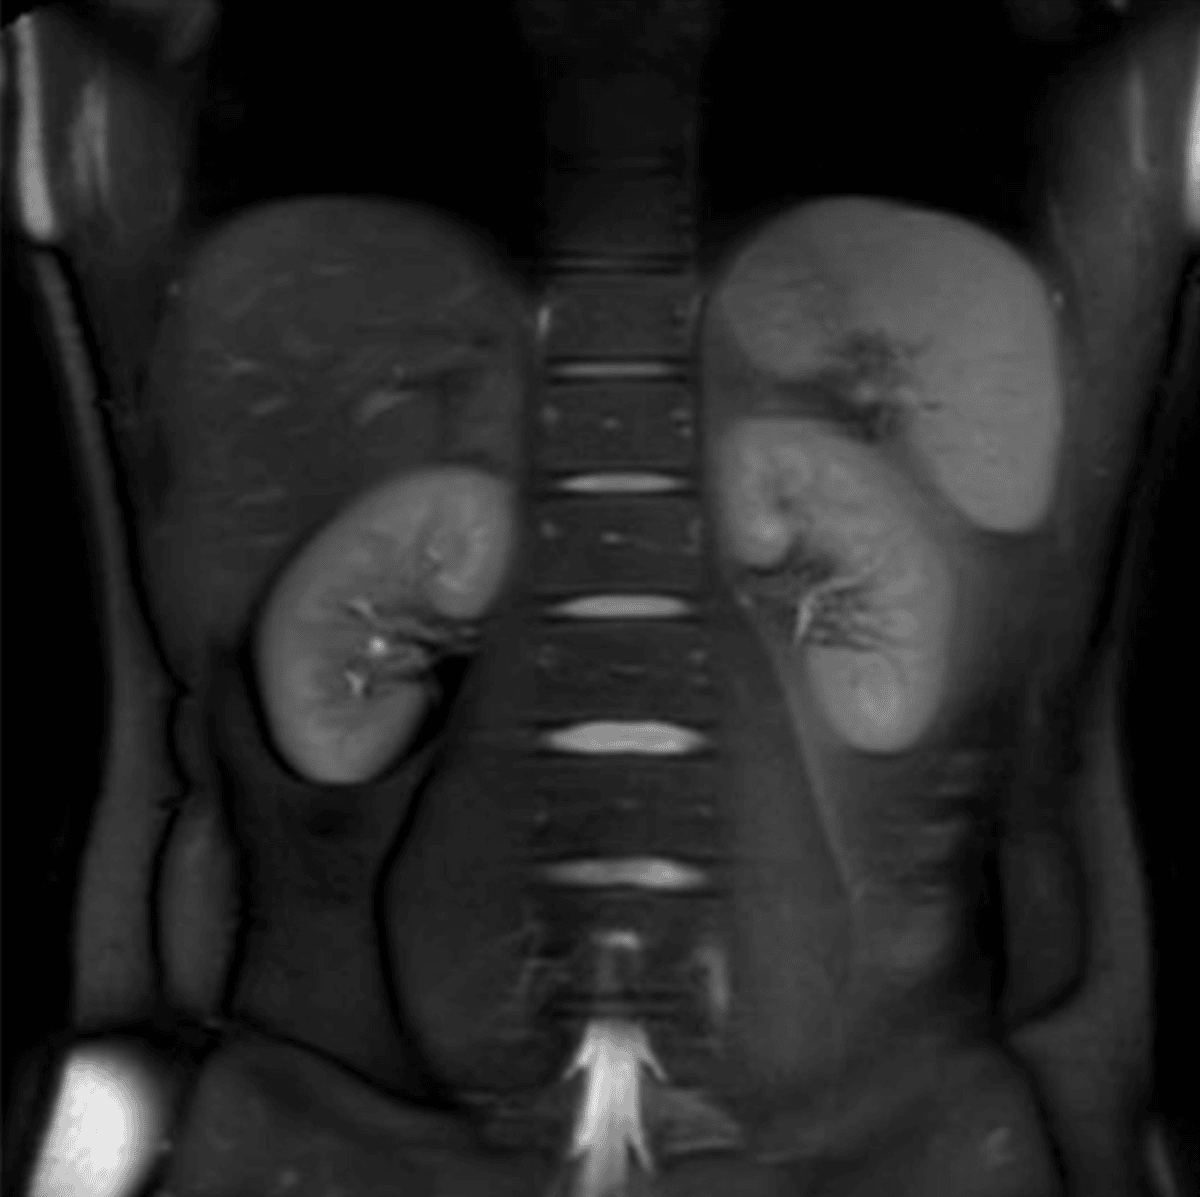

Multi-organ MRI scans, like those from Ezra, can spot early signs of cancer before symptoms arise. This is particularly useful for people with multiple risk factors, providing a quick, painless, and radiation-free screening service.

Image taken from Fig. 2, and used under the Creative Commons license.